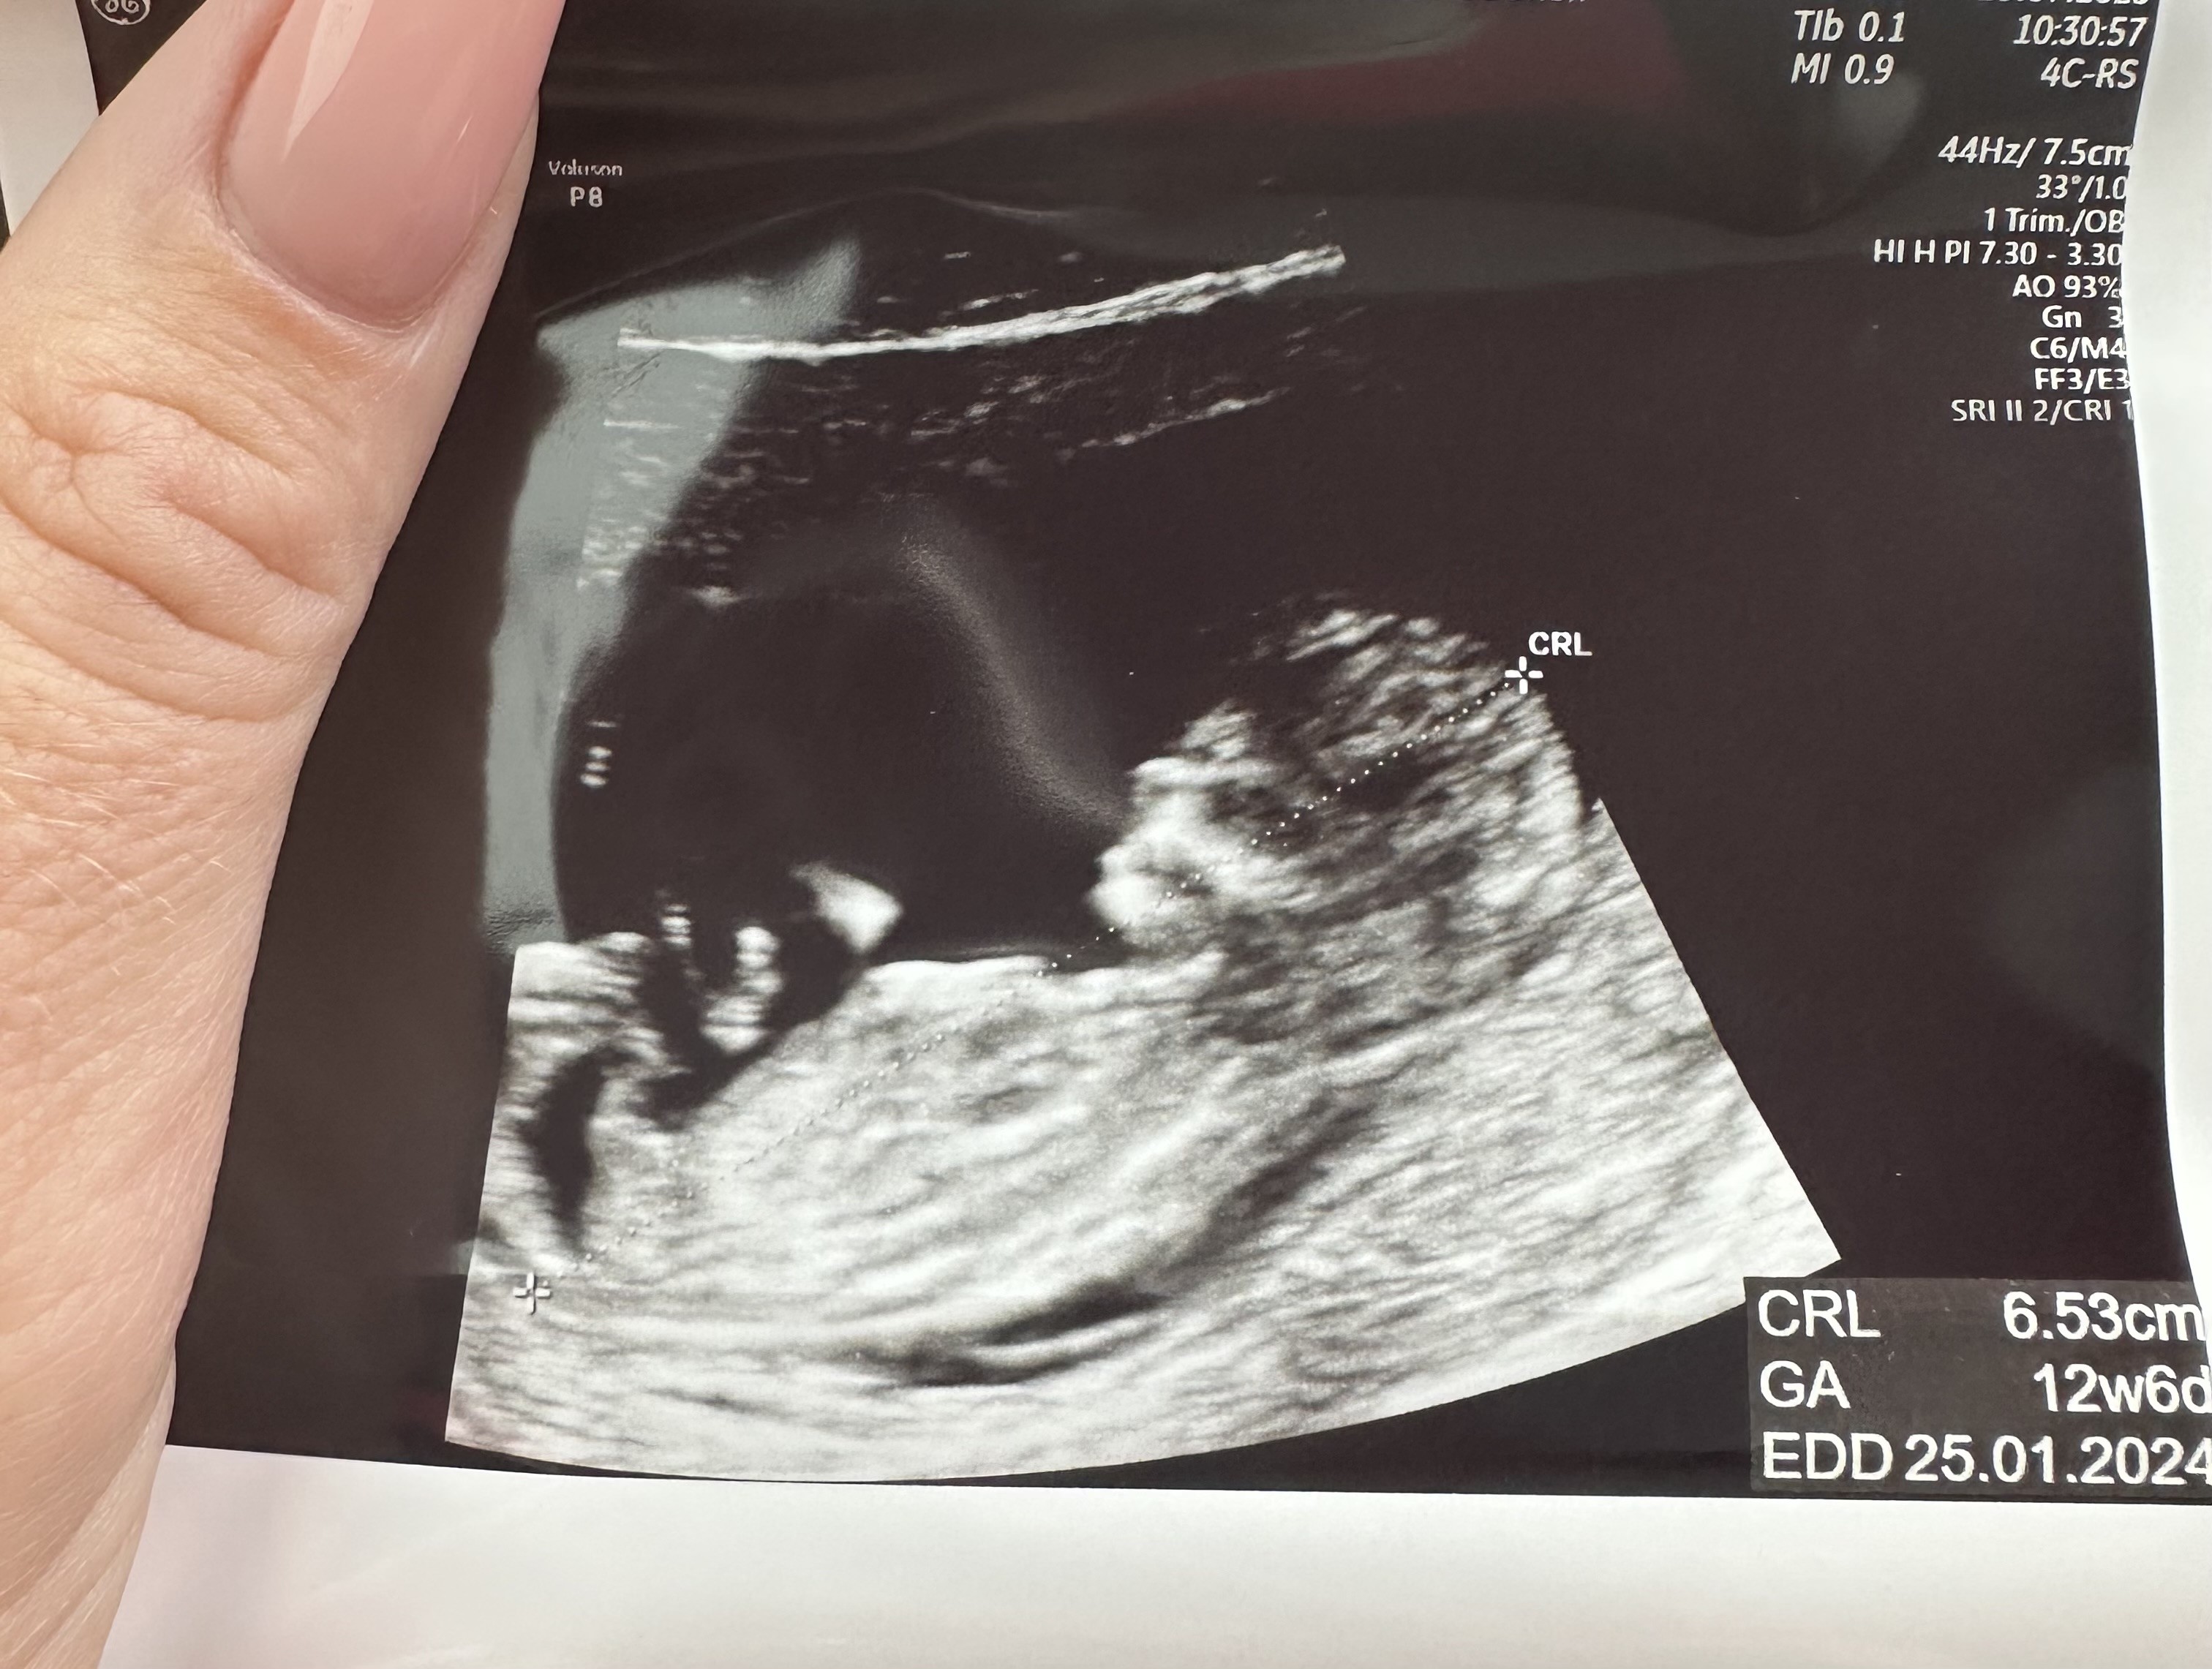

U mnie 4 razy beta nie drgnęła , po wykonaniu badań immunologicznych i zastosowaniu leków 5 transfer okazał sie tym 🩵 i dziś zaczęłam 13 tydzień ciąży 🥹 także trzymam kciuki za podobny scenariusz u Was ✊🏼

Melduje sie i ja po wizycie ✋🏼 a w zasadzie cała rodzinka , bo dziś towarzyszyła mi także córka , która nie mogła sie doczekać 🫶🏽 i mąż. Maluszek rośnie i rozwija sie tak jak trzeba i ... choć dość nieśmiało , ale Doktorka zasugerowała, ze rosnie nam chłopczyk 🥹 🩵🩵🩵

• IMG_6620.jpeg

IMG_6620.jpeg

883,9 KB · Wyświetleń: 76